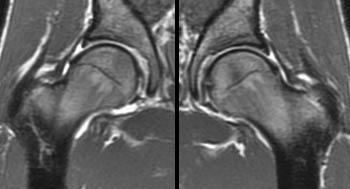

Subscribe to our free newsletters to receive latest health news and alerts to your email inbox. Depending on your condition, your doctor may recommend a hip replacement. Most areas in your body are susceptible to arthritis, and it can change the way you live your everyday life on days that it flares. If your doctor says it's time for a full hip replacement, and you are worried that you will be laid up for months, you're in luck. Being in any kind of pain can be uncomfortable, especially when you're unsure of its cause. It can interfere with your quality of life, especially as you get older. Advocates and companions of the elde. You had trouble with one of your most important joints, and you made a tough decision: While the hard part may be. Use four physical therapy exercises to help strengthen your hip muscles. The hip, its joint and its tissues can withstand quite a bit when it comes to movement and torsion, but even one of the strongest joints and tissues. Typically, the doctor makes one long incision in your hip to remove the bone and. A total hip replacement, also called total hip arthroplasty, is a procedure in which a surgeon removes your hip joint and replaces it with a prosthetic joint.

The hips are the central pivot point of the entire body, supporting its weight during movement and when sta. Pain and stiffness in your hips is more than a nuisance. You had trouble with one of your most important joints, and you made a tough decision: Depending on your condition, your doctor may recommend a hip replacement. A total hip replacement, also called total hip arthroplasty, is a procedure in which a surgeon removes your hip joint and replaces it with a prosthetic joint.